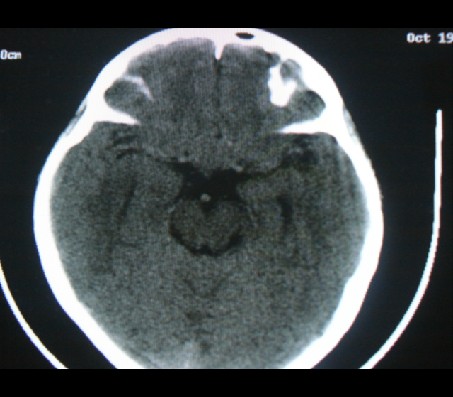

男性,12岁。反复头痛呕吐半月。脑积液无异常。病变部位ct值32hu,dwi无异常。

鞍上为主,累及鞍内,垂体受压位于鞍底。mri呈短t1、长t2信号,不太支持生殖细胞肿瘤,首考颅咽管瘤。

鞍内囊性占位性病变,t1wi、t2wi,均为高信号影。ct平扫为等密度。发病年龄较小。故首先考虑颅咽管瘤,可以做ct增强扫描

鞍内囊性占位性病变,t1wi、t2wi,均为高信号影。ct平扫为等密度。发病年龄较小。故首先考虑颅咽管瘤。